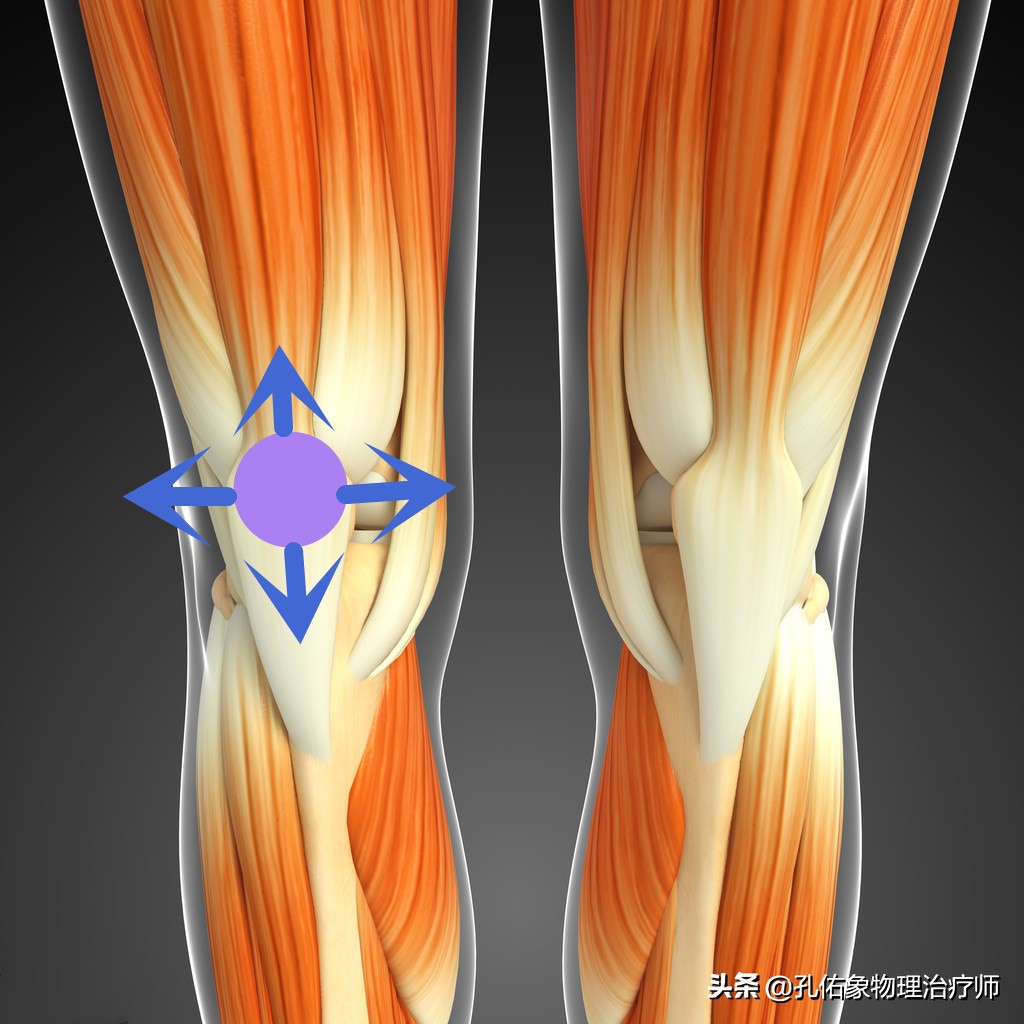

因为膝痛,会使稳定膝盖骨周围的韧带、肌肉打破原有的平衡;比方说现在很多人因不注意锻炼,常见于大腿外侧很紧,而膝盖骨内上缘处的股内侧斜肌就会很弱,从而影响到膝的受力,就会导致小腿发生旋转,最终使脚巴掌发生受力不均的情况下行走,毫无疑问就会出现足底疼痛。

第二步:该怎么治疗

到这里呢,治疗相对就很简单了,因为有前期的精准检查评估判断,你是哪里的肌肉软组织紧张?是哪里的肌肉软组织弱?导致膝盖骨的不稳定,偏移了正常的运动轨迹。只需要根据力学去强化和放松即可,当然理念方向找对了,治疗方法相对不固定,会很多的。

比如说,常见的大腿内侧斜肌和内收肌的离心力量强化训练,臀大肌的离心强化训练;阔筋膜张肌和髂胫束的放松训练;膝关节的本体感知训练等等。